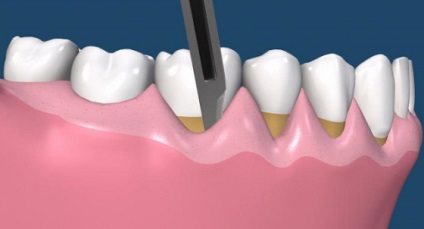

- Este o secțiune orizontală în zona gingiei, gingivală indepartezi de la o margine la o jumătate de milimetru. Această clapă - o fâșie subțire de țesut moale - eliminat, deoarece un astfel de țesut deteriorat niciodată nu va fi capabil să adere la dinte.

- tesutul gingival este jupuit de pe dinte, cu suprafața mucoasei interioare a dintilor - prea.

- Acumulate în pungile parodontale ale plăcii și a țesutului de granulație este îndepărtată, rădăcinile sunt lustruite.

- Gumele tensionat la gât de dinți și sunt reticulate. Suturile sunt suprapuse în spațiile interdentare).